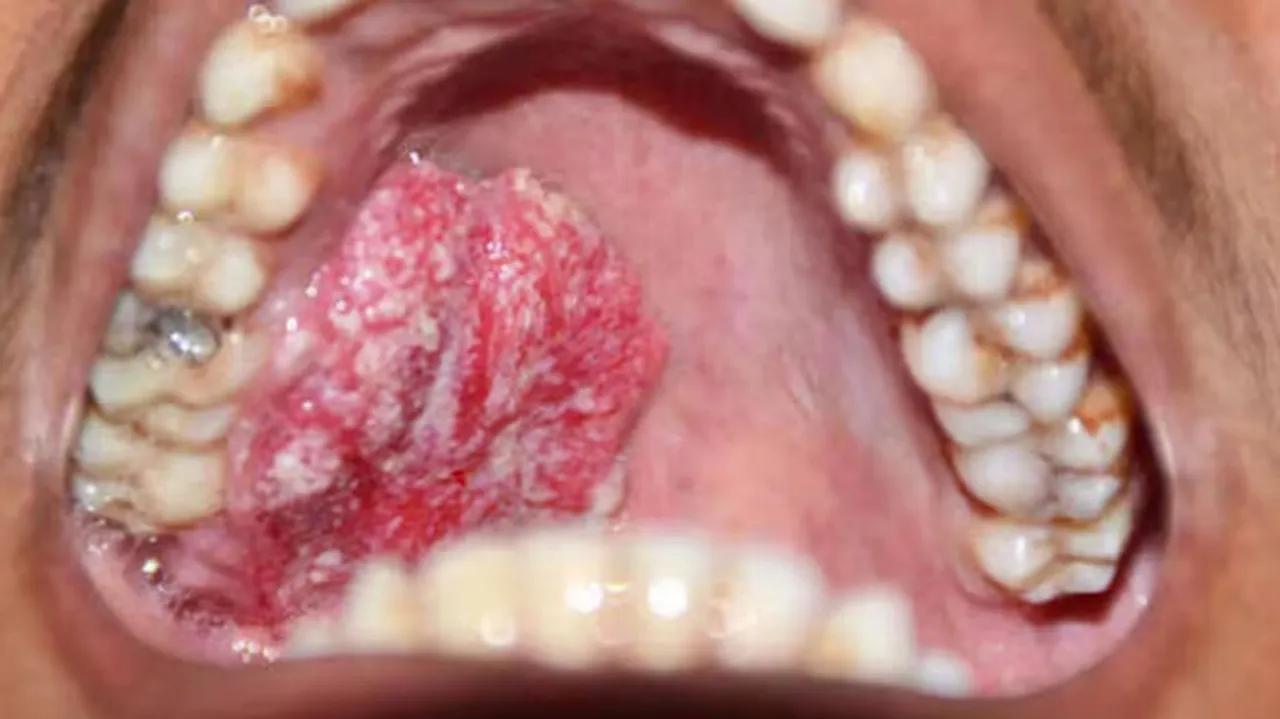

କର୍କଟ ରୋଗରେ, ସର୍ବପ୍ରଥମେ ପାଟିରେ ଅଲସର ହୁଏ। ଏହାର କୌଣସି ପ୍ରକାରର ଯନ୍ତ୍ରଣା ଦେଖାଦିଏ ନାହିଁ। ଏହା ସହଜରେ ଭଲ ହୁଏ ନାହିଁ। ପରେ ଗଳାରେ ଯନ୍ତ୍ରଣା, କାନରେ ଯନ୍ତ୍ରଣା, ମୁଣ୍ଡବିନ୍ଧା ଏବଂ ଗଳାରେ ଫୁଲା ହେବା ସହିତ ଗେଟା ହେବାଯିବା ଆରମ୍ଭ କରେ।

ଯଦି ଏପରି ଲକ୍ଷଣ ଦେଖାଯାଏ, ତୁରନ୍ତ କର୍କଟ ସମ୍ବନ୍ଧୀୟ ଡାକ୍ତରଙ୍କ ସହିତ ପରାମର୍ଶ କରନ୍ତୁ ଯାହା ଦ୍ୱାରା ପାଟି କର୍କଟ ଠିକ୍ ସମୟରେ ଚିକିତ୍ସିତ ହୋଇପାରିବ।